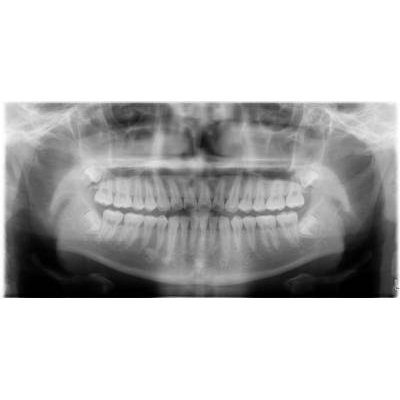

兒童牙科

乳齒:嬰兒出生後第六個月左右第一次長出來的牙會長滿20顆。

預防重於治療。通常在幼兒時期最常見的疾病-齲齒」。愈早作牙齒檢查,便有愈多的機會提早預防牙齒的發生。看牙不一定會痛!在沒有任何的病痛查,對幼兒來說,是一次的愉快經驗。

人工植牙